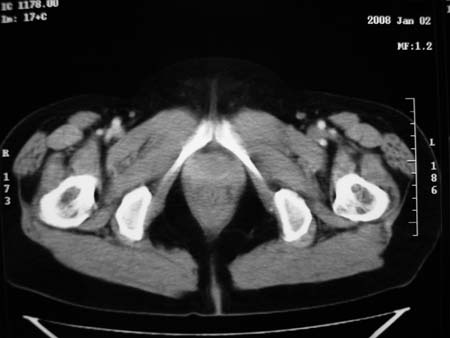

以下是引用卜一在2008-1-2 20:39:00的发言:[br]右侧附件区囊实性肿块,与膀胱壁分界不清,增强后实性部分显示强化。考虑为:右侧卵巢囊腺癌可能性大。支持!

以下是引用zhengfaming在2008-1-2 19:28:00的发言:[br]右下腹腔内附件区可见一囊实性混合密度块影,先考虑囊腺癌